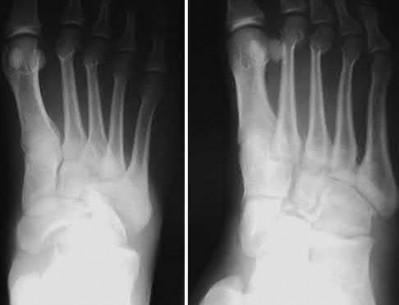

A 25-year-old female is involved in a motor vehicle collision. She presents with the isolated injury seen in Figures A through D. Her leg is swollen but her skin is intact. She has no clinical signs of compartment syndrome. Which of the following treatment options will allow for maintenance of fracture alignment and minimize the risk of soft tissue complications?

The patient presents with a closed distal third metaphyseal-diaphyseal distal tibia fracture with simple intra-articular extension. Immediate intramedullary nailing along with percutaneous fixation of the articular component provides appropriate restoration of length, rotation and alignment and minimizes the risk of wound complication.

Displaced distal third tibia fractures may be associated with simple intraarticular extension. Operative treatment of intra-articular distal tibia fractures has historically been performed with open reduction and internal fixation. Early open reduction and plate fixation of pilon fractures has been associated with high rates of infection and wound complication. In select patterns with simple articular extension, percutaneous screw fixation and medullary nailing may provide appropriate reduction with minimal soft-tissue risk.

Figures A and B demonstrate a distal third tibial shaft fracture with simple intra-articular extension. The axial and coronal CT cuts in Figures C and D further clarify the articular injury. Illustrations A and B demonstrate a comminuted distal third tibial fracture with simple intra-articular extension. Illustrations C and D are fluoroscopic images of the same injury after intramedullary nailing and percutaneous fixation of the articular component.